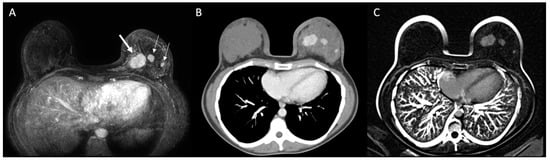

The main tumor was identified on MRI and MDCT in all cases. Table 1 summarizes imaging findings on both modalities and agreement between them. At breast MRI, mean tumor extension was 4.6 cm (median: 3.9 cm; SD: 3.3 cm; range: 1.4–12.2 cm). At MDCT, mean tumor extension was 4.5 cm (median: 3.2 cm; SD: 3.2 cm; range: 1.3–13.0 cm). There was a good agreement on tumor extent between these methods (ICC: 0.868; 95% CI: 0.732–0.935; p < 0.001), and both were considered concordant in 28 cases, of which 21 had less than 6 mm difference in tumor extent. Compared to MRI, MDCT overestimated tumor extension in one case (3.0%) and underestimated tumor extension on four cases (12.1%). Multicentricity was characterized in both methods in 10 patients (30.3%) (Figure 3), and only in MDCT in one case (3.0%). There were no contralateral malignant lesions in our sample. In four cases (12.1%), there were suspicious axillary lymph nodes on MDCT, which were not identified on MRI (three were confirmed as malignant and one negative for malignancy after biopsy). In eight cases (24.2%), MDTC showed a higher number of suspicious axillary lymph nodes when compared to MRI, including level II and/or III in five cases.

Figure 3. Patient with multicentric invasive breast carcinoma in the left breast. Breast MRI (A) identified the main tumor (thick arrow) and two additional lesions on the same breast (thin arrows), which were also identified on MDCT ((B): post-contrast; (C): subtraction).